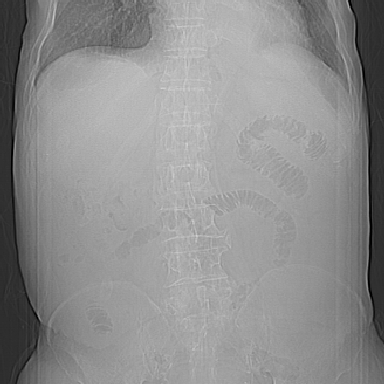

以下是引用qian在2006-12-4 19:11:00的发言:[br]胸腔和腹腔内均见有液性影,肝上极包膜下有一较大椭圆形低密度影,密度均匀,边缘清晰,结合病史考虑术后肝脓肿并胸腹腔积液。

以下是引用chry3在2006-12-4 21:05:00的发言:[br]应该往上扫几层,我考虑膈下脓肿。[br]大家考虑:胃部手术怎会造成肝内脓肿,隔下脓肿到是会造成的

以下是引用dyqct在2006-12-4 19:54:00的发言:[br]考虑:1、肝包膜下脓肿;[br] 2、少量腹水;[br] 3、右侧少量胸膜腔积液。